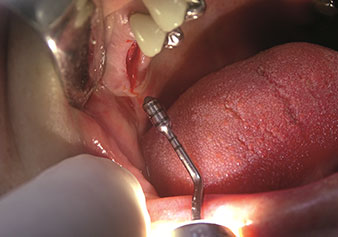

Gestione alveolare

Un’applicazione che viene spesso sottovalutata è l’estrazione atraumatica di radici di denti o frammenti di radici nell’ambito della gestione alveolare. I periotomi sottili, che sono attualmente disponibili in due versioni (EX1 ed EX2 di W&H), possono essere, inoltre, utilizzati per rimuovere con facilità denti che hanno precedentemente subito uno specifico trattamento endodontico o con radici anchilosate. Ne consegue l’estrazione di alveoli in cui i tessuti duro e molle sono entrambi completamente intatti in quanto è generalmente possibile evitare la riflessione.

Ciò pone le basi ottimali per un trattamento con impianto immediato o successivo (Figure 1 e 2 inserite grazie alla gentile concessione del Dott. Torsten Conrad, Bingen a. Rhein).

Foto: © Dott. Torsten Conrad (Bingen a. Rhein)